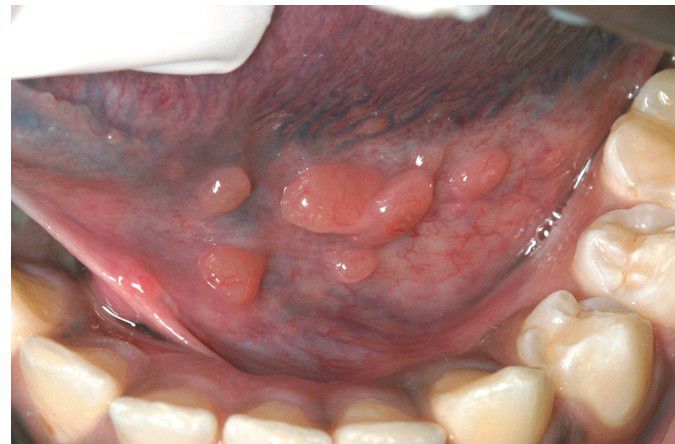

Lymphoid Hyperplasia

. Multiple prominent lymphoid aggregates in the floor of the mouth.